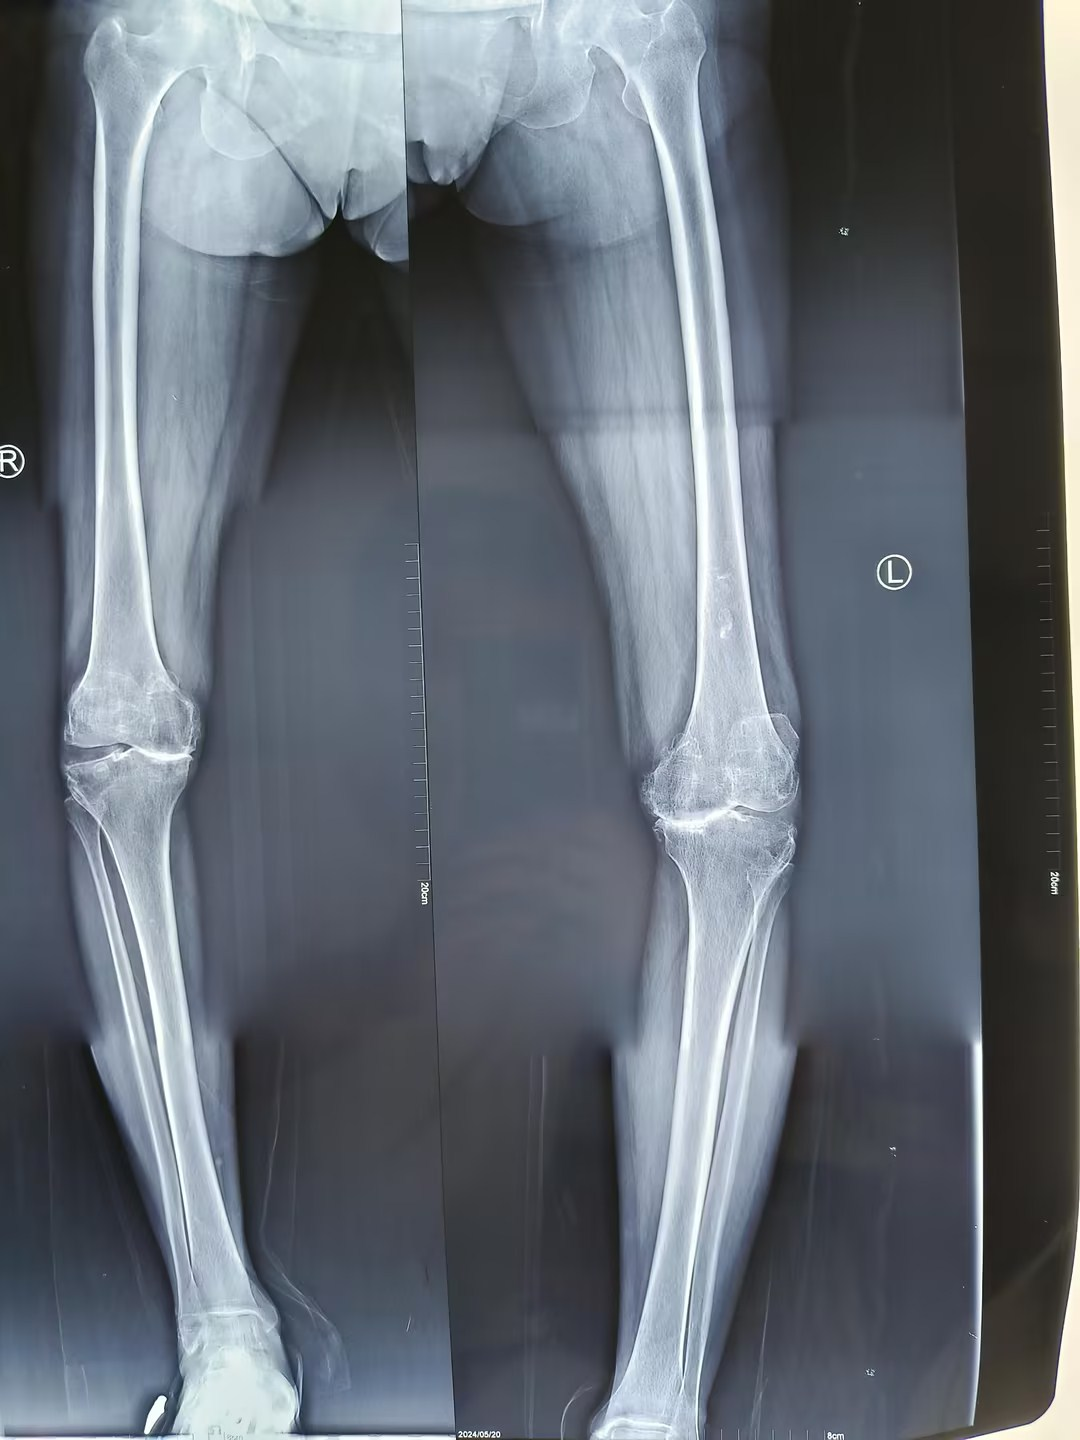

在创伤骨科住院后,经安勇主任医师团队诊断,王先生为双侧膝关节骨性关节炎,双侧膝关节内翻畸形。结合病史及影像学检查,考虑行双侧膝关节置换手术,因王先生左膝疼痛较右膝疼痛明显,所以先行左膝关节置换手术,术后10天,患者左膝疼痛减轻后,再行右膝膝关节置换手术。手术取得圆满成功,解除了王先生十余年的病痛。